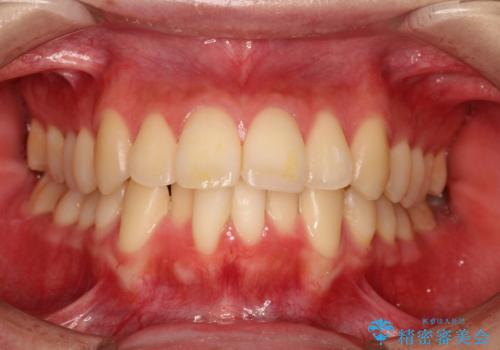

- 前歯が出ているため口が閉じにくく、横顔が気になるとのことで来院された患者様です。。

上下の前歯が前方に傾斜しており、口唇の突出感がありました。